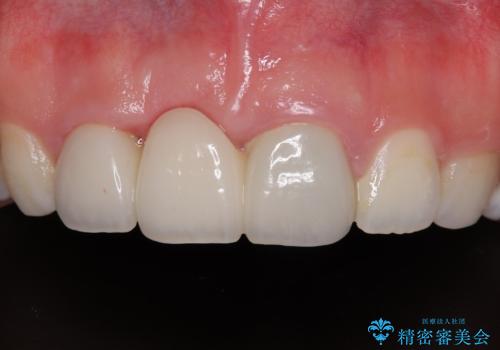

歯肉ラインを整えるために歯肉移植術を行うか悩んでいましたが、行わないという判断をされたため、やや不揃いの歯肉ラインとなりました。